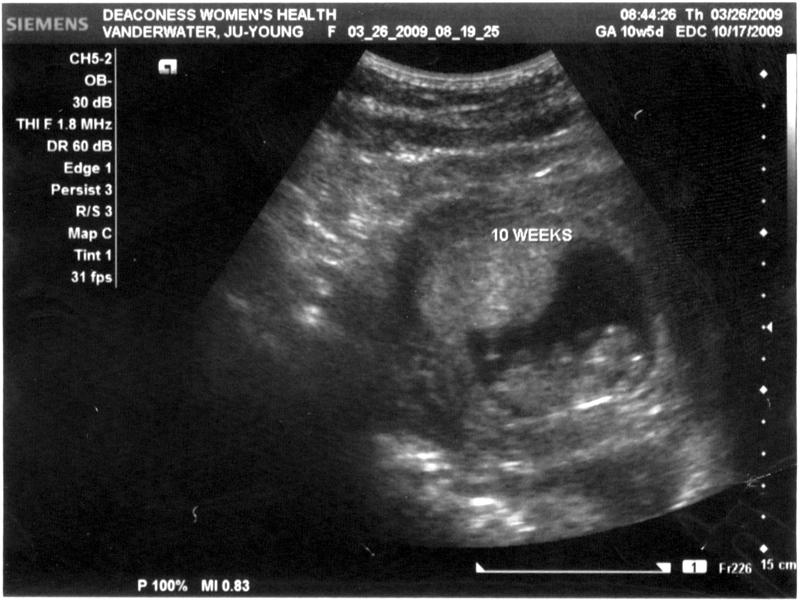

Anyway.  Fast forward 8 weeks.  I'm 12.5 weeks along now,  and still full of worry and paranoia.  I thought after a couple of doctor's appointment, seeing the heart beat of the baby, I would calm down.  But no such luck.  I still wake up in the morning, wondering if the baby is safe and sound.  This is why some women get dopplers I guess.  It's a little better than earlier weeks, but at week 12, I still worry.  My next appointment isn't until the 23rd of April, so I'm getting really antsy.  Kris calls it "ultrasound withdrawl".  I had some spotting earlier (weeks 6 and 8), which really got us worried, and because of the spotting, we got a couple of early ultrasounds in.  Now that I won't get one for four more weeks, I'm just going crazy!

10 Week ultrasound

Ultrasound at 10 weeks